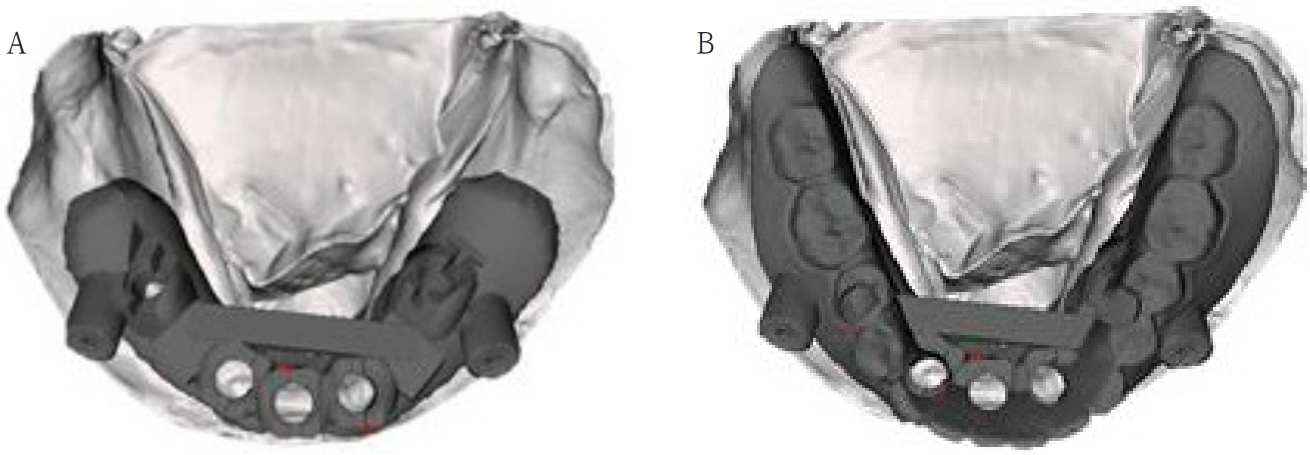

Fig. 8.

A. Under part of surgical guide with fixation pin is situated on dental stone cast. B. Upper part of surgical guide is overlapped with under part.